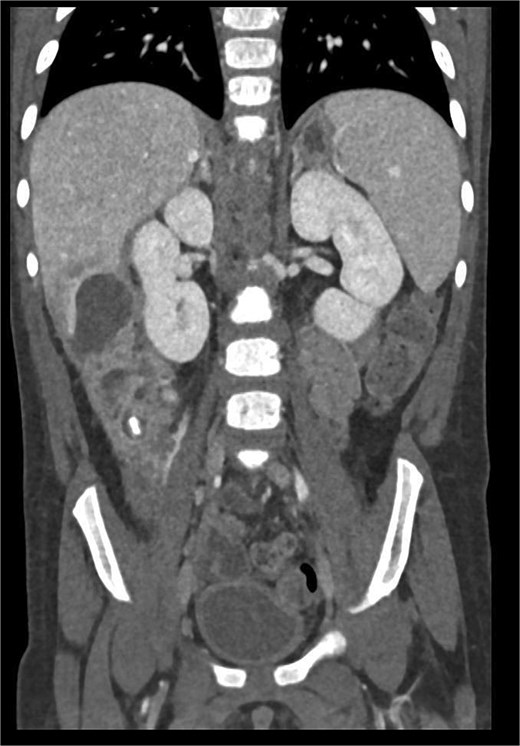

CT imaging of the abdomen (Fig. 2) revealed a retrocecal appendix in its typical location, measuring 50 mm in length and 14 mm in diameter, with a thickened wall (5.5 mm). A proximal fecalith measuring 3 × 3 × 14 mm was identified. Post-contrast enhancement of the appendix wall was noted. Adjacent to segments V and VI of the liver, a fluid collection with an air-fluid level was observed, measuring 5.3 × 3.8 × 4.5 cm, surrounded by a 3 mm enhancing capsule, consistent with a hepatic abscess. A second, smaller hypodense collection measuring 13 × 22 × 11 mm was found inferior to the primary abscess. Additional findings included reactive lymphadenopathy (up to 8 × 4 mm) and free fluid in the right iliac fossa (up to 12 mm). Other abdominal organs, including the liver, pancreas, kidneys, and spleen, appeared normal. The findings were consistent with complicated acute appendicitis and associated abscesses.

CT imaging of acute appendicitis with fecalith and multiple hepatic abscesses.